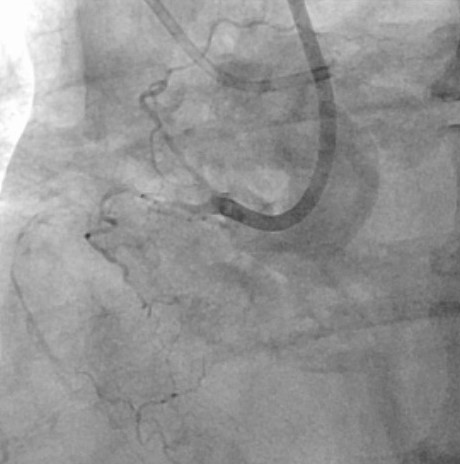

患者的左边血管堵塞也极其严重,主干道狭窄99%,合并钙化、弥漫、分叉,在预扩张球囊呈现明显的“腰征”的情况下,罗裕主任果断选择了旋磨治疗,1.5mm的磨头5次后通过,最后成功植入两枚支架。

左图术前左冠,右图术后左冠